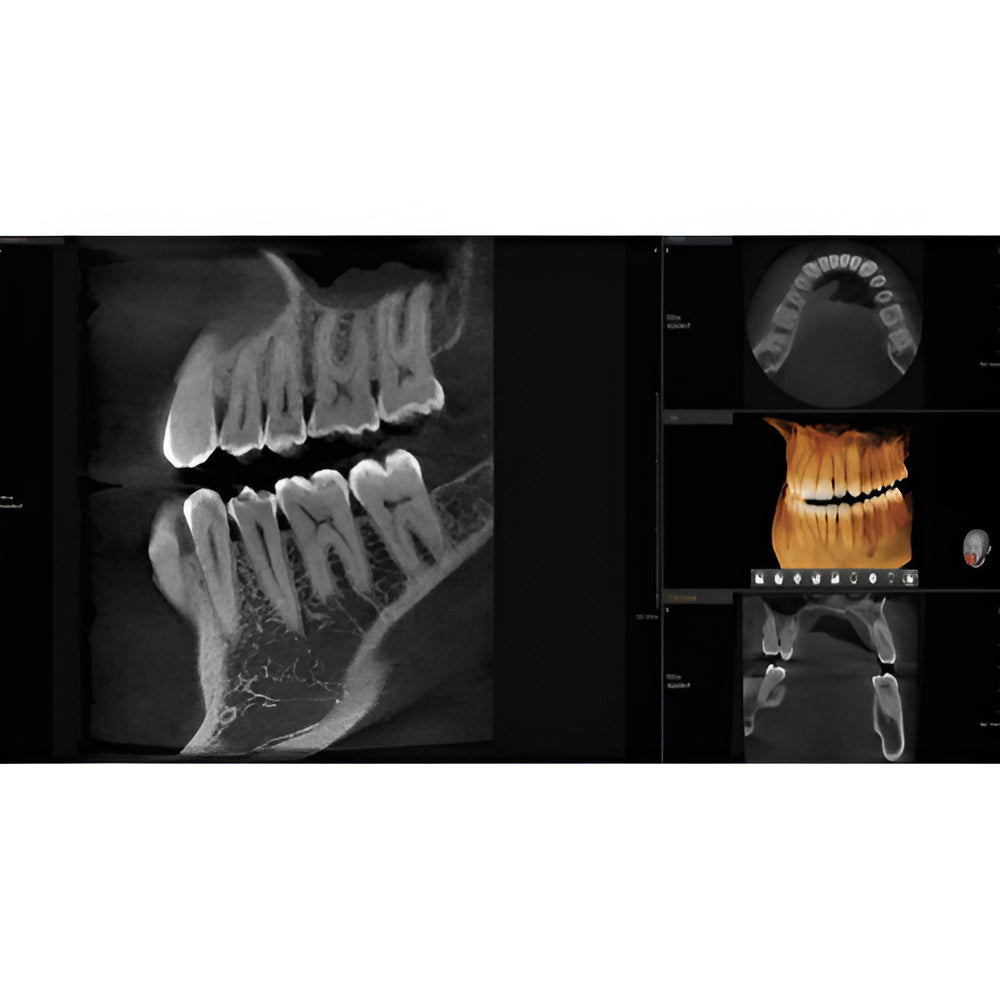

The Vatech PaX-i3D Green panoramic plus cone beam system delivers large field of view (up to 15 x 15 cm) dental CBCT scans in addition to standard 2D panorex and extraoral bitewing X-ray images. This Vatech CBCT machine features the innovative green CT technology which minimizes patient dose, while the Rapid Scan feature delivers high-quality 3D cone beam scans in just 5.9 seconds. A quick exposure time helps to minimize artifacts and motion, while at the same time reducing patient dose, making your imaging process more efficient and safer.

- EZ3Di Imaging Software with License

- Dedicated Panoramic

- Panoramic

- 3D Cone Beam

- Bitewing Program